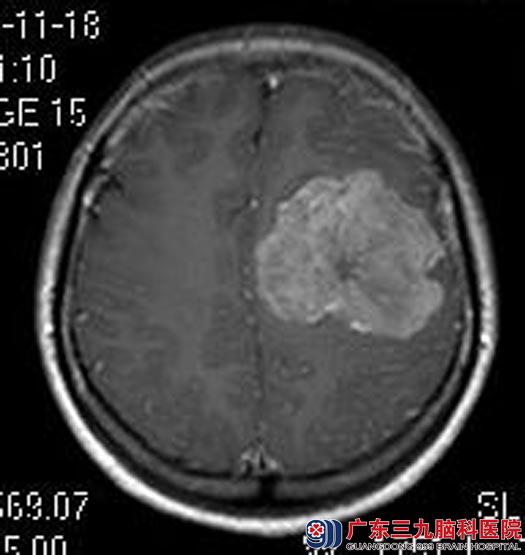

入住广东三九脑科医院综合神经外科,头颅MRI示:左侧额顶部颅骨内板下示类圆形占位,大小约64.2mm×50.3mm×41.6mm,考虑脑膜瘤。